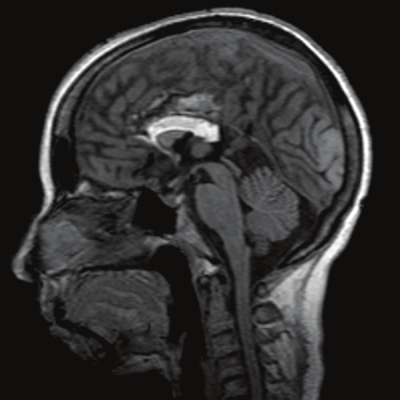

MRI não thai có cần thiết không?

MRI não thai giúp đánh giá chi tiết hơn cấu trúc não. Đặc biệt là vỏ não và chất trắng.

MRI thường được thực hiện sau tuần 20. Giá trị cao hơn sau tuần 26 khi cấu trúc vỏ não phát triển rõ hơn.

Trong các bất thường thể chai, MRI có thể phát hiện thêm tổn thương phối hợp mà siêu âm chưa thấy rõ. Điều này ảnh hưởng trực tiếp đến tư vấn tiên lượng.

Giá trị của MRI phụ thuộc chất lượng siêu âm ban đầu.